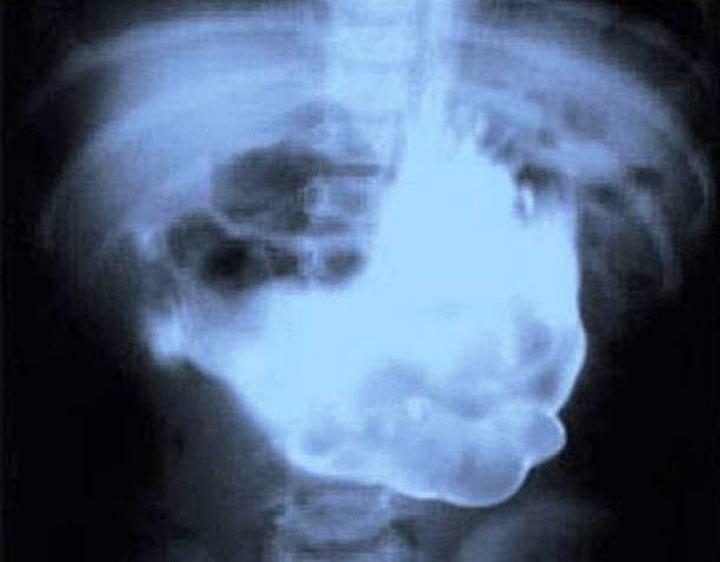

1. Эта женщина по неизвестным причинам проглотила 78 столовых приборов